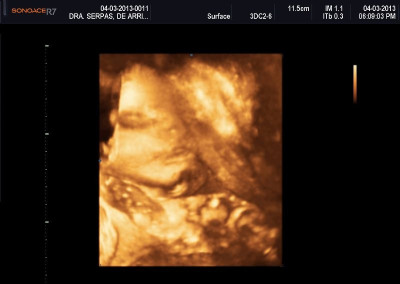

Varias ultrasonografías en 2D y 3D

Envíado por Dr. Nelson Menjívar Sarco